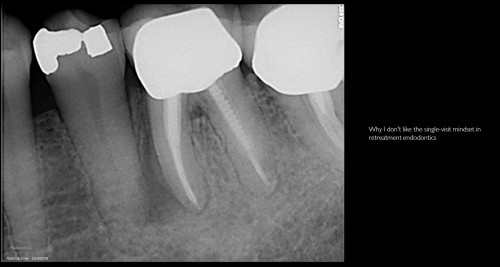

Single visit mindset

By Gary Carr / January 22, 2019

Patient in for a sinus tract check recall today asking questions…… All treatment done by […]